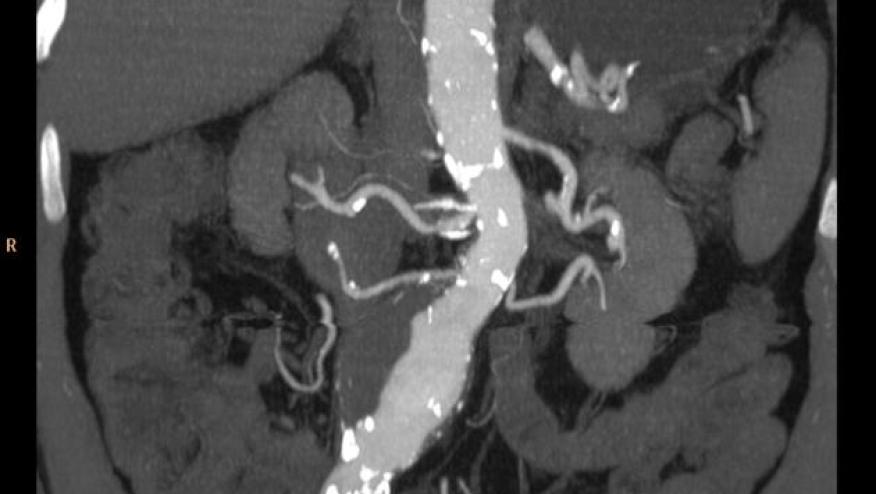

In GCA patients, aortitis is a severe manifestation, potentially leading to aneurysms and aortic dissection.

Multicenter observational study included 196 patients with GCA-associated aortitis documented. Aortitis was identified using 18F-FDG PET/CT scan.